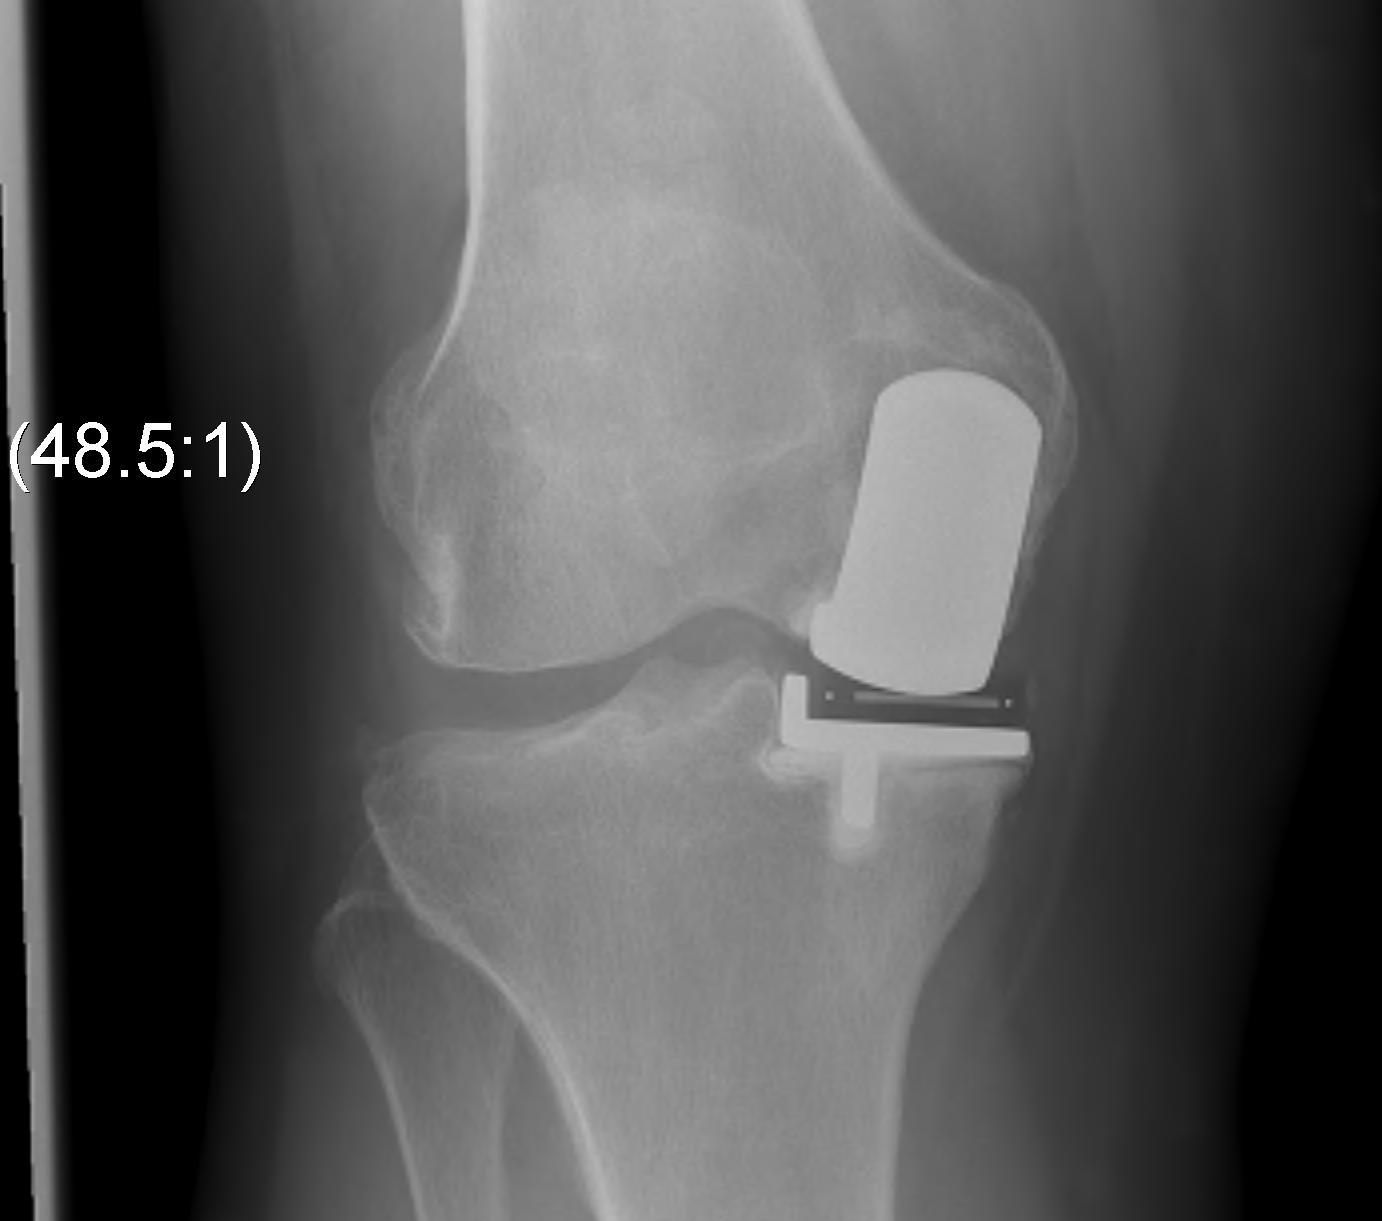

Patient 1

Patient 2